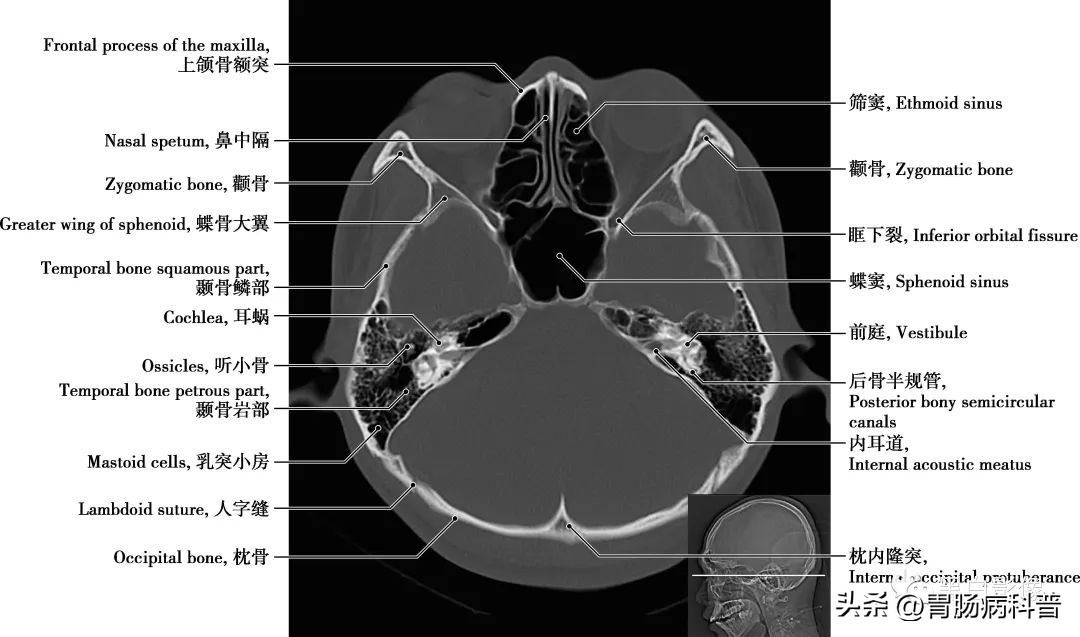

图1-2-15 经第四脑室下部轴位切面

耳蜗 为内耳的一个解剖结构,和前庭迷路一起组成内耳骨迷路,是传导并感受声波的结构,位于骨前庭的前内侧,形似蜗牛壳,耳蜗的中轴称蜗轴,呈圆锥形,由一条骨蜗螺旋管环绕蜗轴旋转二又四分之三圈而成

图1-2-16 经第四脑室侧孔轴位切面

颈内动脉 分为颅外段又称颈段,自颈总动脉分叉处至颅底。颅内段分为七段:C 1 颈段、C 2 岩段、C 3 破裂(孔)段、C 4 海绵窦段、C 5 床段、C 6 眼段和C 7 交通段。分支分布于视器和脑